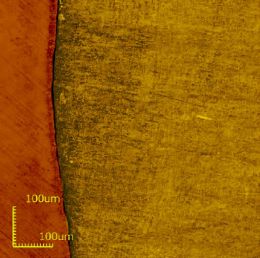

The use of a confocal laser microscope such as the Olympus LEXT OLS4000 leads to higher resolution as compared to a contact stylus as the microscope’s laser beam has a resolution of 0.4 μm. This is compatible with standard demineralization and does not cause damage on the sample surface because there are no contact forces between them (Figure 1).

Figure 1: Profilometry analysis of eroded dental enamel by hydrochloric acid.

Left side: corresponding control area. Right side: corresponding eroded area.